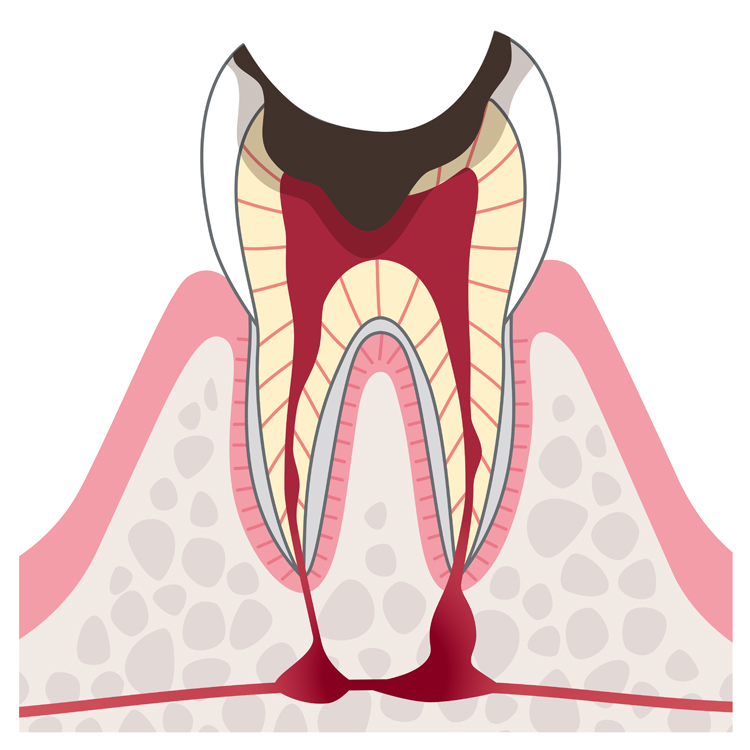

精密根管治療とは読んで字のごとく、根管(歯の根っこ部分)の治療のことを指します。なぜ根管を治療するかというと、虫歯や歯周病菌などのバイ菌がその根管部分まで到達してしまい、その中にある神経や歯髄なども細菌に汚染されてしまっている状態だからです。

もちろん抜歯することもできますが、根管部分の細菌を死滅させ、洗浄し薬剤を充填して根管を閉じるという治療をすれば、抜歯せずとも根管(歯の根っこ)部分を温存することができるのです。

そうすると感染した部分を全て取りきれないという問題や、誤って根管を破ってしまい、根管の先に感染した細胞が残ってしまうことで結局は抜歯しなければならないという事態を生むケースも多くあります。